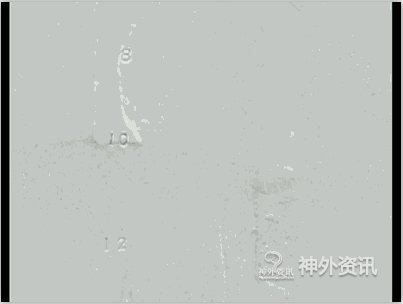

图9: E. 2D-DSA正侧位动态影像。

图9: F. 2D-DSA正侧位动态影像。

图9: H. 术后2D-DSA正侧位动态影像,瘘口已消失术后双下肢肌力恢复至五级。

图9: I. 术后2D-DSA正侧位动态影像,瘘口已消失术后双下肢肌力恢复至五级。